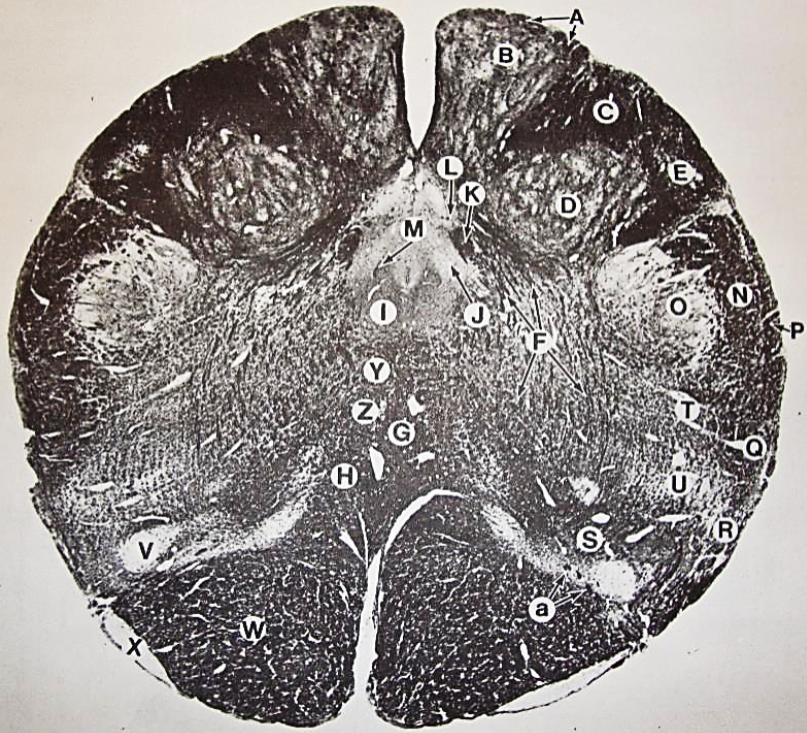

A

posterior median sulcus

B

posterior intermediate sulcus

C

anterior median fissure

D

gracile fasciculus

E

Gracile nucleus

F

fasciculus cuneatus

G

spinal trigeminal tract

H+I collectively

spinal trigeminal nucleus

J

Accessory nucleus

K

pyramidal decussation

L

lateral corticospinal tract

M

rubrospinal tract

N

posterior spinocerebellar tract

O

anterior spinocerebellar tract

P

lateral spinothalamic tract

Q

anterior spinothalamic tract

R

lateral vestibulospinal tract

S

medial longitudinal fasciculus

T

tectospinal tract

U

central canal